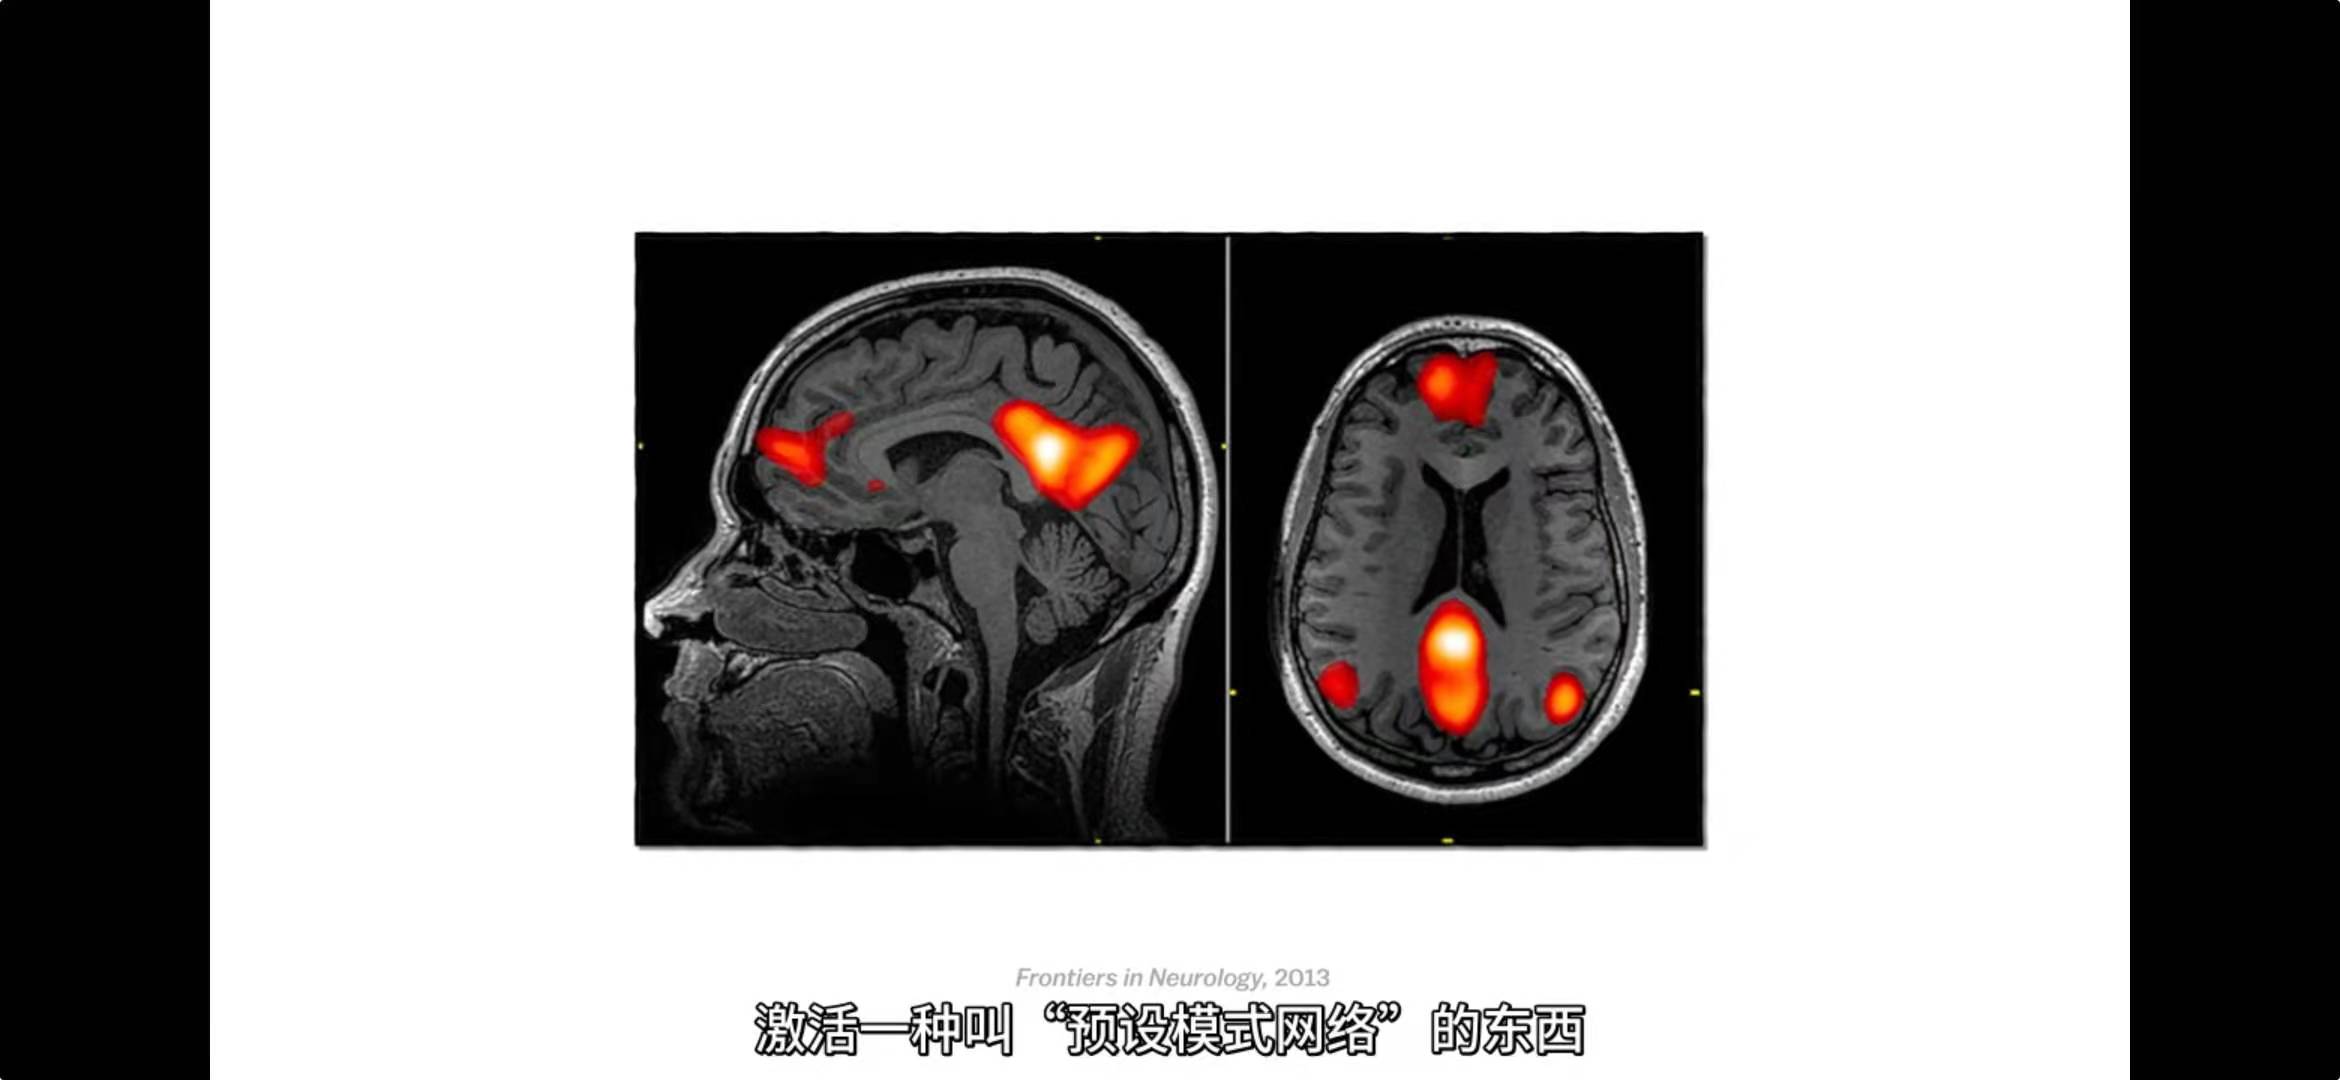

头脑解密 The Mind, Explained (2019)

从梦境到焦虑症,这部由奥斯卡奖得主艾玛·斯通讲述的具有启发性的剧集带您探索大脑内部的活动。